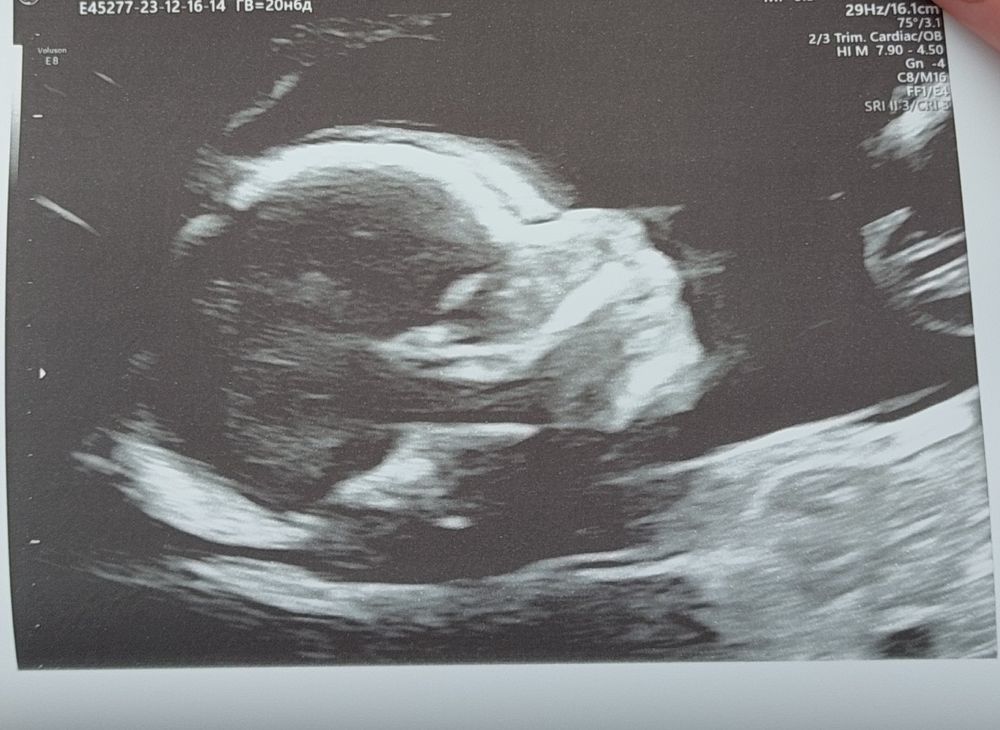

2 скрининг!!!

Анализы, скринингиПрошли в субботу 2 скрининг

, пошла платно, так как в жк древний аппарат, да и гин сказала идти платно с моими рисками. По узи все отлично, малышка активная,не хотела чтобы её измеряли🤭, ни каких потологий нет и слава богу🙏. Конечно глубоко внутри страх есть,что может родиться больной ребёнок, но я стараюсь не думать о плохом,и все таки надеюсь на ошибку,пока не рожу и не увижу ,что все хорошо ,наверное не успокоюсь🫣.Желаю всем здоровых детишек🙏🙏🙏.